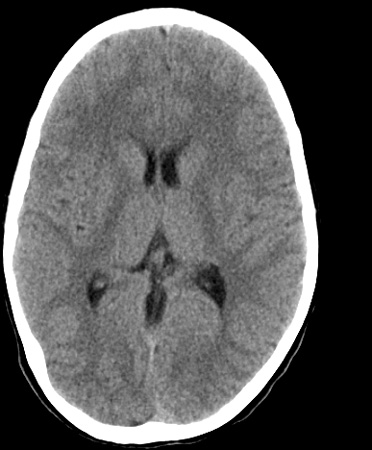

Identify the following structures in the head CT. To view the location of the structure in the image click on the label at the left and an arrow will point to the structure in the image.

Internal Capsule

Pineal Gland

Septum Pellucidum

Straight Sinus

Thalamus